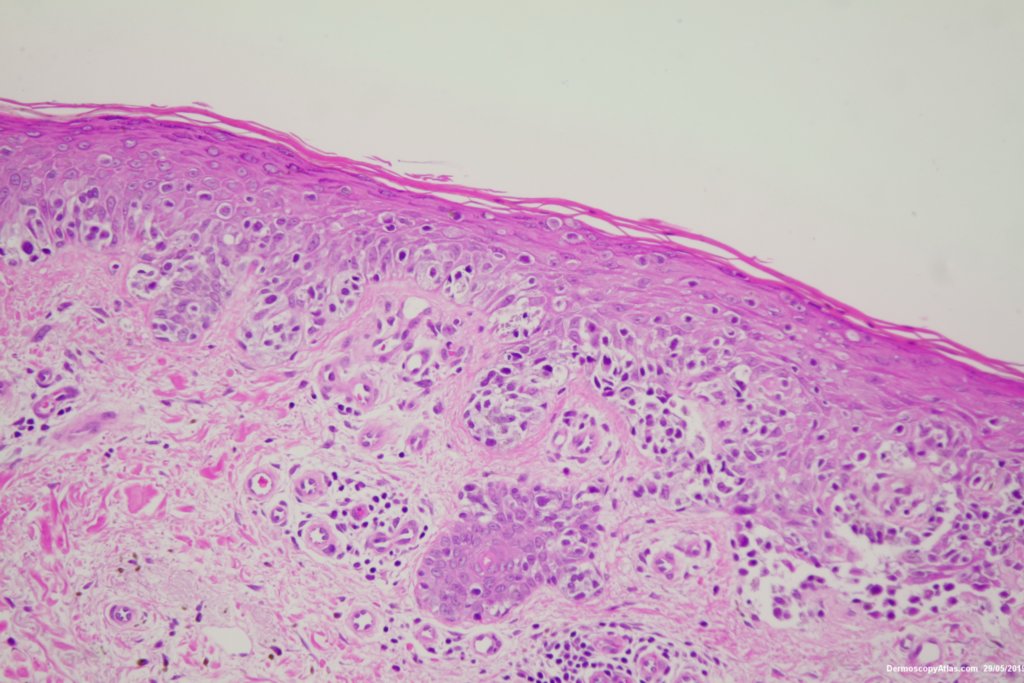

Diagnosis: Melanoma invasive

This was an invasive melanoma 0.4 mm thick but the histology shown shows mainly in situ melanoma.Have a look at the second case in the video below for a more detailed overview of the histology.